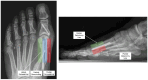

Illustrated anteroposterior and lateral radiographs highlighting key radiographic features of the percutaneous osteotomy healing classification including medial, central, and lateral remodeling zones and the presence of visible osteotomy lines.